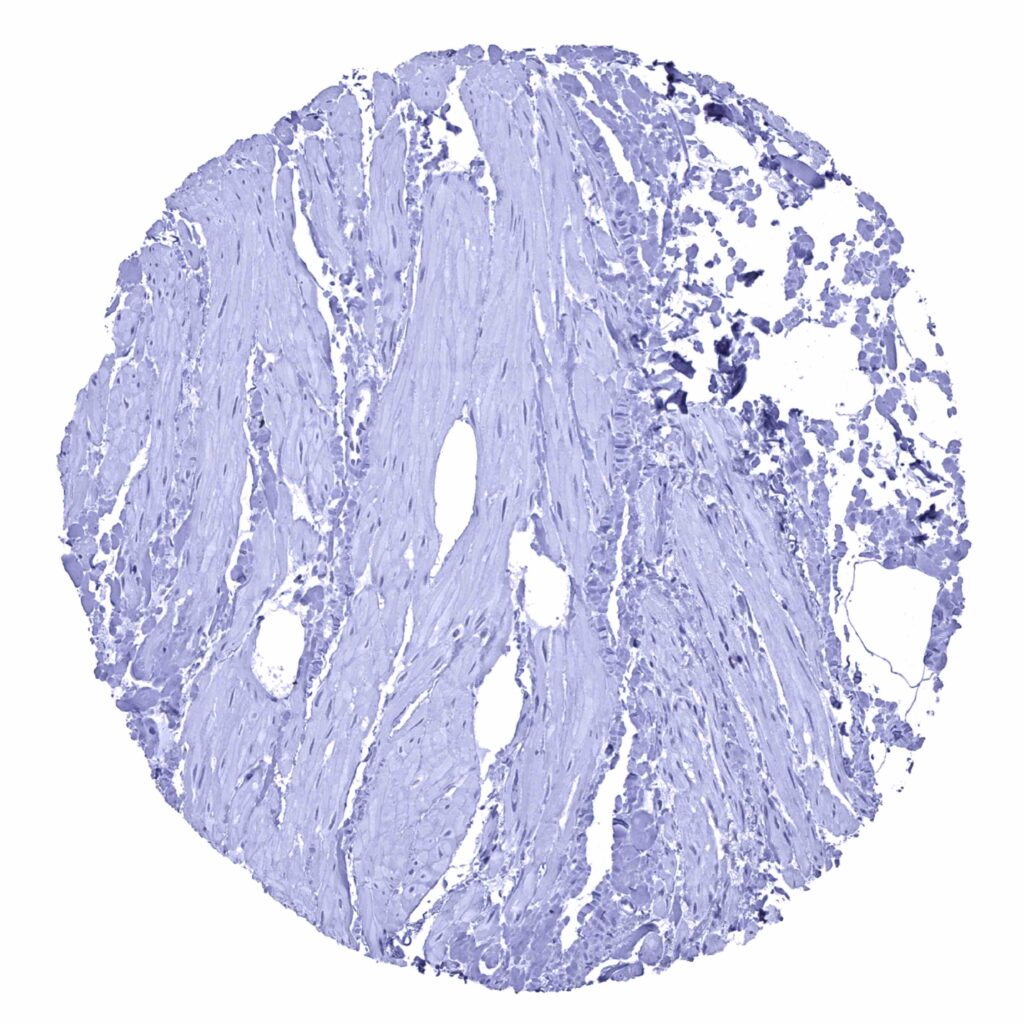

Urinary bladder, muscular wall